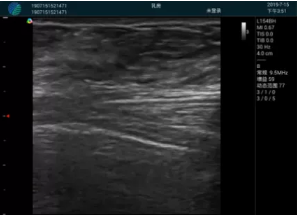

可視化甲狀腺穿刺引導(dǎo)

頸動(dòng)脈血流充盈飽滿,無外溢

肝內(nèi)血管顯示清晰,血流敏感無外溢

甲狀腺囊性結(jié)節(jié),囊壁鈣化,透聲好

甲狀腺囊性占位

2001年美國健康護(hù)理研究和質(zhì)量監(jiān)督局(AHRQ)批準(zhǔn)了一項(xiàng)關(guān)于提高患者安全性的報(bào)告,建議:在頸內(nèi)靜脈中心置管術(shù)時(shí)使用超聲引導(dǎo)。此后超聲引導(dǎo)穿刺被用于幾乎所有的急診穿刺操作,尤其是血管穿刺。

便攜超聲在急診穿刺中的應(yīng)用: